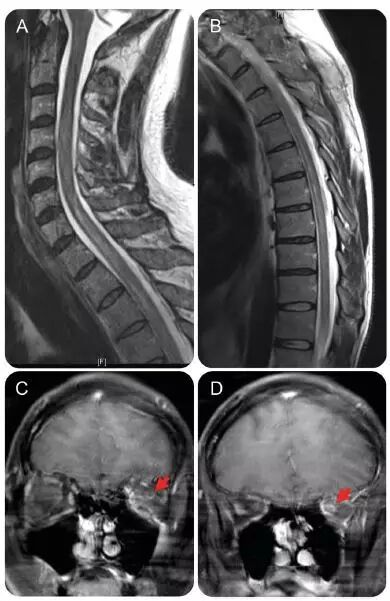

患者脑脊液细胞数增多提示 GBS 可能性较低,目前仍考虑脊髓病变;经验性给予阿昔洛韦、万古霉素、头孢曲松钠等治疗,对脑脊液进行多种病毒感染的检测。再次进行脊髓核磁检查显示,左侧视神经强化,T2 像显示 C6-T9 段脊髓广泛高信号(见下图);颅内 MRI 无异常。

图 1 患者颈胸段脊髓核磁表现。颈段(A)和胸段(B)MRI 显示 C6-C9 节段脊髓信号异常;头颅 MRI 增强 T1 像(C,D)显示左侧视神经强化信号(箭头所示)